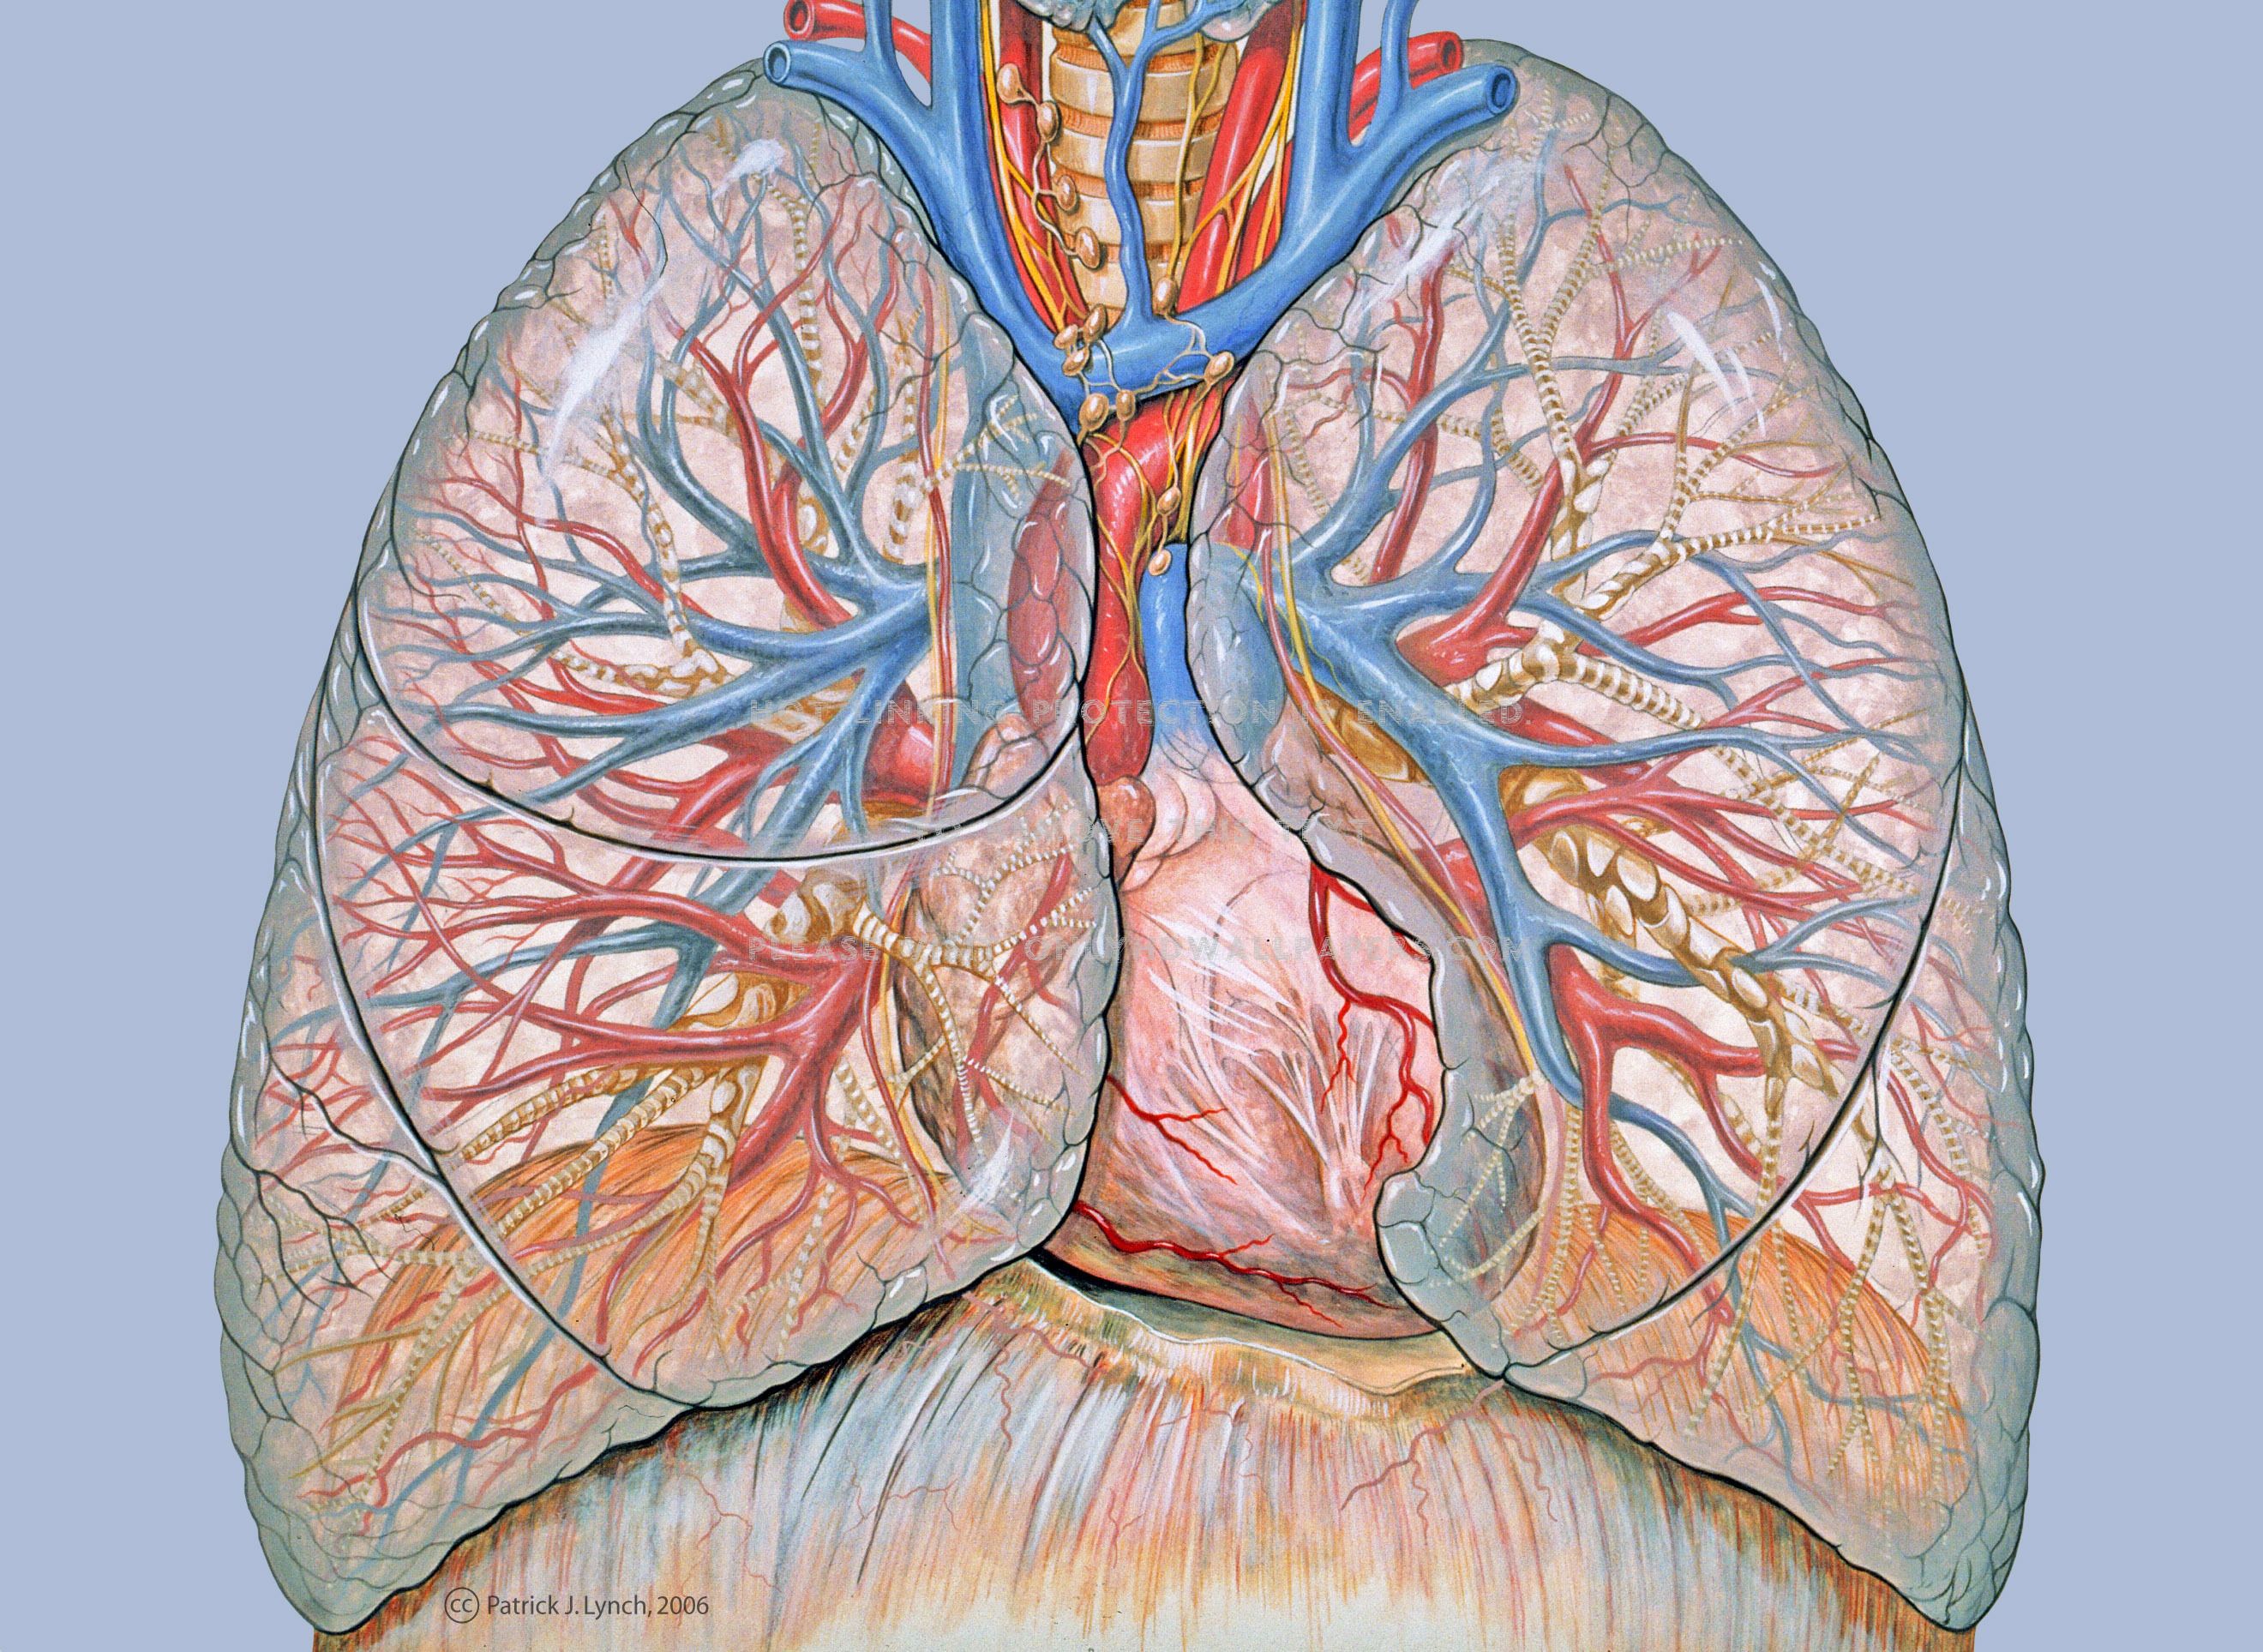

HD Medical Wallpaper (61+ Images)

getwallpapers.comwallpaper medical hd lungs anatomy full

getwallpapers.comwallpaper medical hd lungs anatomy full